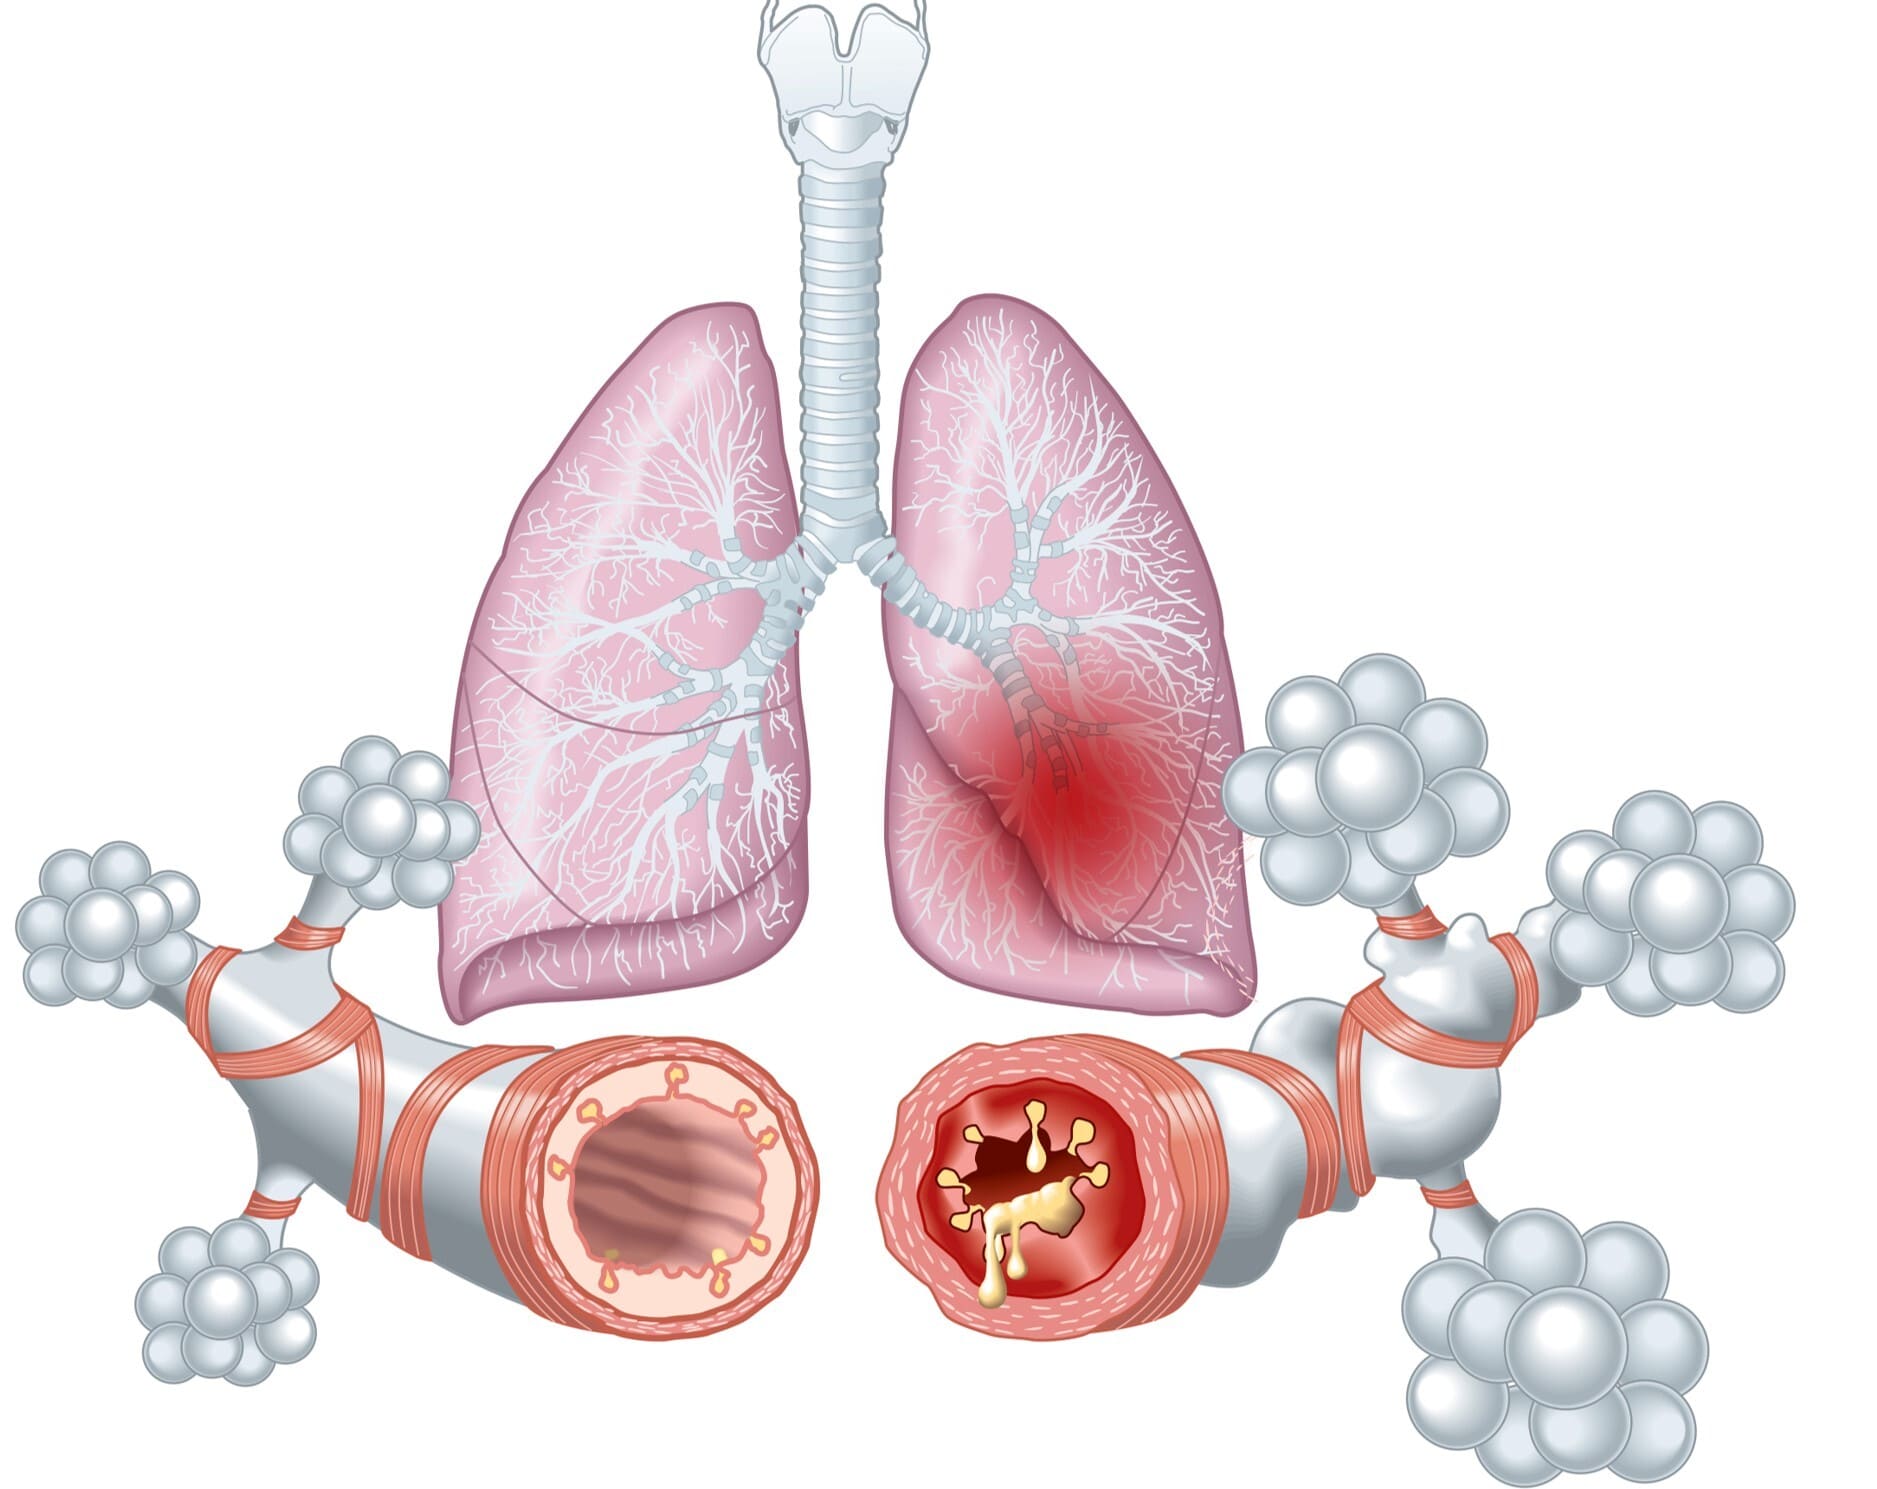

Astma is een chronische longziekte die niet overgaat. Symptomen van astma zijn benauwdheid, moeite met ademhalen en hoesten. Astma-aanvallen kunnen veroorzaakt worden door bepaalde stoffen die je inademt of flinke inspanning. Bij astma zijn de luchtwegen altijd ontstoken, wat leidt tot meer slijm en een dikker slijmvlies in de longen. Medicatie kan helpen om de luchtwegen weer open te zetten en het ademen te vergemakkelijken.

COPD is een chronische longziekte waarbij de longen altijd ontstoken zijn, wat leidt tot blijvende schade aan de longblaasjes. Deze schade is niet meer te genezen. De oorzaken van COPD kunnen onder andere een erfelijke ziekte zijn, maar vooral ontstaan door roken.